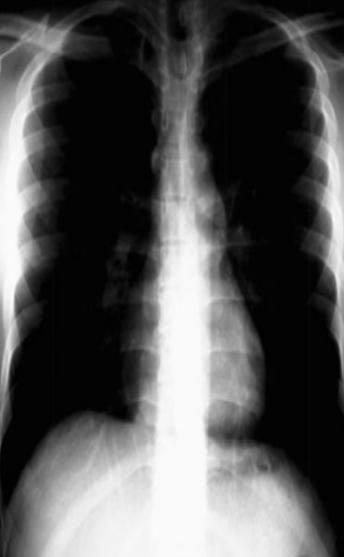

COPD patient

diaphragm flat

barrel chest on lateral view (AP diameter increase)

widened intercostal spaces

lungs hypper enflated→globular heart

Hidden area showing hiatal hernia